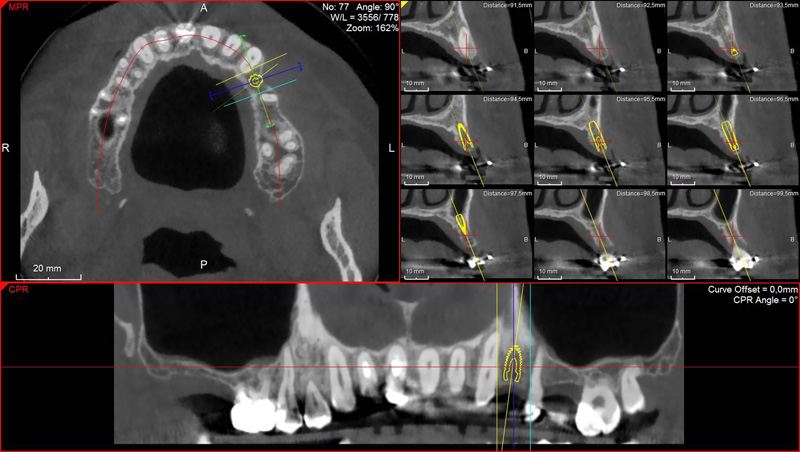

Pro následné plánování využíváme počítačové programy NewTom Implant Planning a coDiagnostiX, které slouží na plánování vhodných pozic pro zavedení implantátů, operačních šablon, kostních bloků, pozdějších protetických náhrad, ...

Pomocí počítačových programů – NewTom Implant Planning a coDiagnostiX si lékař sám provádí veškerá potřebná zobrazení a měření.

NewTom Implant Planing

Jedná se o plánovací program, který využívá dat získaných při vyšetření pomocí přístroje New Tom. Tento program umožňuje tříprostorovou počítačovou simulaci při plánování pozic implantátů.

Součástí programu je i databáze, ve které mohou být uloženy všechny typy implantátů od všech výrobců, včetně jejich délek, průměrů i tvarů.

Lékař si vytvoří všechny typy zobrazení potřebných pro naplánování – tedy 2D snímky (panoramatický), příčné řezy i 3D model.

Vidí zde i důležité anatomické útvary – čelistní dutinu, průběh nervu atd. Po proměření množství kosti – šířky i výšky vybere z databáze vhodný typ implantátu a umístí ho do požadované lokality.

Ihned vidí jeho pozici ve všech 3 rovinách a na všech snímcích i 3D modelu. Může upravovat podle potřeby jeho pozici, sklon atd.

Všechny vybrané a správně umístěné simulované implantáty se ukládají do „počítačové karty“ pacienta s jejich pozicí, délkou, průměrem, typem i sklonem.

Lékař i pacient tedy ještě před vlastní operací vidí, jak by mělo ošetření probíhat a vypadat.

coDiagnostiX – Dental Wings

Jedná se o externí plánovací program, spojený se zubní laboratoří a frézovacím centrem, který využívá dat získaných z 3D rentgenu čelisti, otisku zubů a dásně (scanu zubů a dásně) a finálního návrhu protetické náhrady.

Tento program umožňuje tříprostorovou počítačovou simulaci při plánování pozic implantátů. Součástí programu je i databáze, ve které mohou být uloženy všechny typy implantátů od všech výrobců, včetně jejich délek, průměrů i tvarů.

Vidí zde i důležité anatomické útvary – čelistní dutinu, průběh nervu atd. Po proměření množství kosti – šířky i výšky vybere z databáze vhodný typ implantátu a umístí ho do požadované lokality. Ihned vidí jeho pozici ve všech 3 rovinách a na

všech snímcích i 3D modelu. Může upravovat podle potřeby jeho pozici, sklon atd.

Všechny vybrané a správně umístěné simulované implantáty se ukládají do „počítačové karty“ pacienta s jejich pozicí, délkou, průměrem, typem i sklonem. V programu také lékař navrhuje chirurgické šablony pro řízenou nebo navigovanou implantaci.